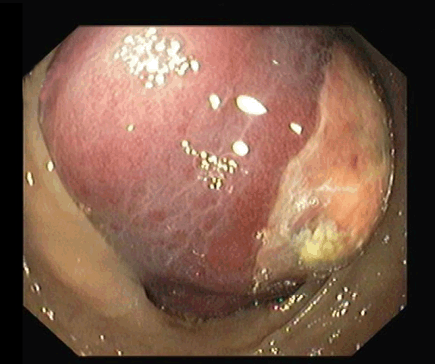

A 70-year-old male went to the emergency room with a 24-hour history of hematochezia preceded by pain in the right lower quadrant. The patient denied fever, weight loss, anorexia or vomiting. He was passing flatus and stools. His past medical history included ischemic heart disease, left renal neoplasia with nephrectomy two years previously and without evidence of recurrence, appendectomy in the childhood, right inguinal hernia repair, hyperuricemia, dyslipidemia, hypothyroidism treated with levothyroxine and colonic diverticula. On physical examination the patient was hemodynamically stable, afebrile and with pain on deep palpation of the right lower quadrant. Bright red blood was observed in the rectum. No other abnormal findings were noted. Blood tests demonstrated mild anemia (hemoglobin 11.2 g/dL) without leukocytosis or neutrophilia and elevation of C-reactive protein (88 mg/L). Renal and liver functions were normal. A colonoscopy was performed. Endoscopy revealed a violaceous mass with ulcerated/necrotic surface obstructing the lumen in the descending colon (Figure 1). After the colonoscopy the patient had an abdominal computed tomography scan that revealed a lipomatous ovoid tumor with 65 mm of major axis with origin in the ascending colon but with top ographic change, because of a complication: colic-colic intussusception with the typical donut sign (Figure 2). The patient underwent surgery that confirmed a lesion with 65 mm and origin in the colonic margin of the ileocecal valve that caused the intussusception. A right hemicolectomy was performed. The histopathology confirmed the diagnosis of giant lipoma with origin in the submucosa. | ||||||

Colonic lipomas are common findings during routine colonoscopy. They are benign lesions usually located in the right colon with decreasing incidence from the cecum to the sigmoid colon. They usually arise from the submucosal layer, but can extend into the muscularis propria, while up to 10% are subserosal. Classically, endoscopic findings described for lipoma are three: the mucosa being elevated over the lipoma with the biopsy forceps (tent sign), indentation of the lipoma with the biopsy forceps (cushion sign) or the "naked fat sign" where the fat can be extruded after biopsy. When typical endoscopic findings are present and they are asymptomatic lipomas do not need additional study or follow up. However, when the typical endoscopic findings are absent additional study with endoscopic ultrasound and/or surgical resection should be considered. Surgical resection should also be considered when they become symptomatic. Lipomas larger than 4 cm in size (giant lipomas) can become symptomatic in 75% of patients. They can manifest as abdominal pain, alteration in bowel habits, gastrointestinal bleeding, perforation, obstruction or intussusceptions. Intussusceptions are an uncommon complication of colonic lipomas and usually limited to one segment of the colon but can extend to more than one segment in some cases [1] [2]. Patients with this complication can present with abdominal pain and gastrointestinal bleeding. Abdominal computed tomography scan is the preferred diagnostic method, as the imaging characteristics of the tumors are typical for adipose tissue with the typical donut sign. Colonoscopy can show a mass with necrotic areas and ulcerated mucosa. Due to the nature of this lesion (subepithelial) biopsies are often inconclusive. The distinction between a colonic lipoma complicated with intussusception from other lesions (malignant epithelial or subepithelial) may be impossible based only on endoscopic aspects. Surgical resection is the treatment of choice when giant lipomas are complicated by intussusceptions. | ||||||